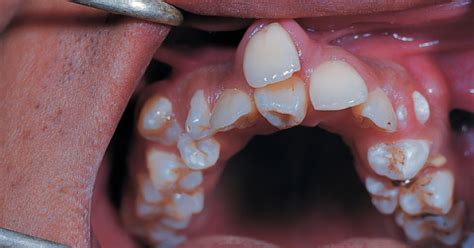

Los dientes supernumerarios son piezas dentales adicionales que aparecen en la boca además de los 20 dientes temporales o 32 dientes permanentes que conforman la dentición normal. Este fenómeno también es conocido como hiperdoncia y puede presentarse tanto en la dentición primaria como en la permanente, aunque es más frecuente en esta última.

Estas piezas dentales extras pueden tener una forma, tamaño y posición normales o presentar alteraciones morfológicas. Su presencia puede pasar desapercibida en algunos casos o provocar complicaciones importantes, dependiendo de su ubicación y relación con los demás dientes.

Tipos de Dientes Supernumerarios

Existen diferentes tipos de dientes supernumerarios, clasificados según su ubicación y forma:

- Mesiodens: Ubicado en la línea media entre los incisivos centrales superiores. Un diente supernumerario que se desarrolla en la zona de los incisivos centrales superiores recibe el nombre de “mesiodens”.

- Distomolar: Localizado distal al tercer molar. También se conoce como “cuarto molar”. Distomolar: cuando la muela de más se encuentra detrás de la muela del juicio.

- Conoidales: Tienen una forma cónica y son predominantes en la región anterior del maxilar.

- Tuberculados: Poseen múltiples cúspides o tubérculos y suelen localizarse en la región molar.

- Odontomas: Son malformaciones odontogénicas complejas que pueden ser compuestas (parecidas a dientes pequeños) o complejas (masa amorfa de tejidos dentales).